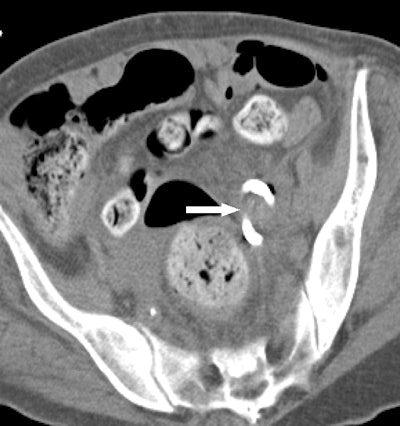

At Brigham, radiologists some time ago modified F-Spoon by cutting a keyhole-shaped notch in the spoon that made it better for guiding needle interventions during CT fluoroscopy studies. By inserting a needle into the keyhole notch, radiologists could compress the abdomen to move bowel loops aside while inserting needles, and they could also keep their hands out of the x-ray beam.

First, they performed a CT scan of the original F-Spoon and imported the file into a computer-aided design (CAD) software application. They used the software to make several modifications based on feedback they had received from physicians, such as changing the device's handle to make it easier to use with either hand, and narrowing the device's neck to make it easier to fit into an ultrasound probe cover -- an important consideration for sterile interventional environments. The CAD file was then converted to the stereolithography (STL) format and output to a 3D printer.

Ultimately, 15 procedures were deemed "questionably feasible" but difficult to perform without the paddle, four were rated as "not feasible" without the device, and two were categorized as feasible without the device but facilitated by the use of it. A particular benefit was the ability to use the paddle to steer the needle by applying pressure against it from inside the keyhole.